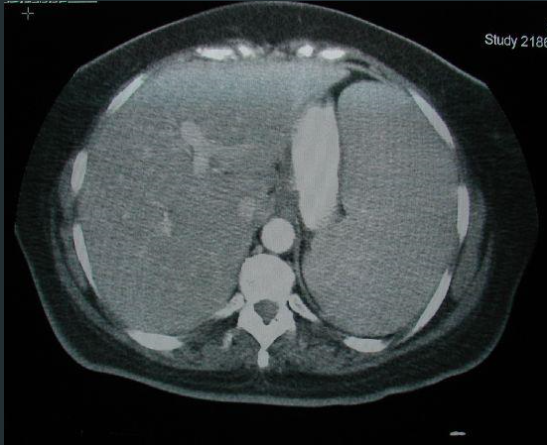

AUMENTO DO BAÇO

POSSÍVEL AUMENTO DO FÍGADO

ESTÔMAGO CHEIO DE CONTEÚDO.